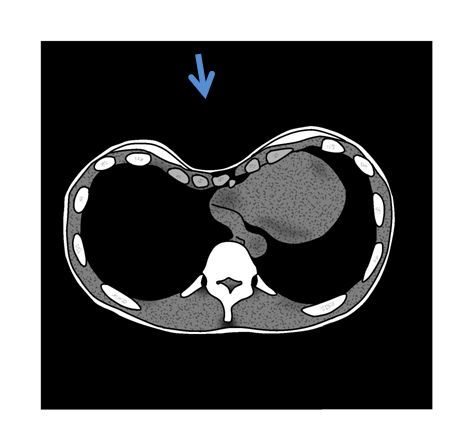

CTでみるとこんな感じの方もいらっしゃいます。

いわゆる漏斗胸という状態の方です。